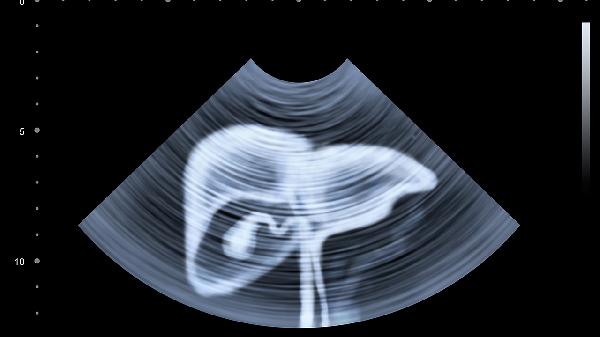

保护肝脏需要长期坚持健康生活方式。40岁以上人群建议每年进行肝脏超声和肝功能检查,出现食欲减退、皮肤黄染等症状应及时就医。日常可饮用菊花枸杞茶等养肝茶饮,但不宜替代正规治疗。保持乐观心态,避免情绪剧烈波动对肝脏功能的影响。